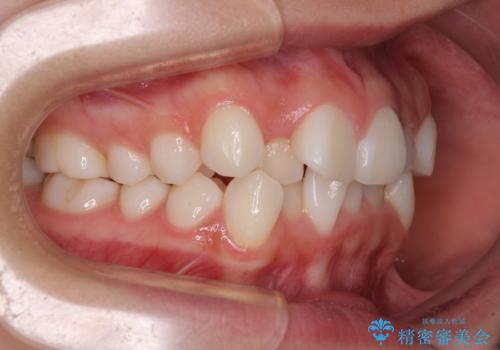

- 歯のデコボコや八重歯、クロスバイトを気にして来院された患者様です。

上下左右第一小臼歯4本を抜歯し、ワイヤー装置にて歯列を整え、さらには少しでも口元を引っ込めるよう矯正治療を行うこととしました。

上下の骨格での左右差が小さかったことと、抜歯矯正であったことで、上下正中の位置をきれいに合わせることができました。